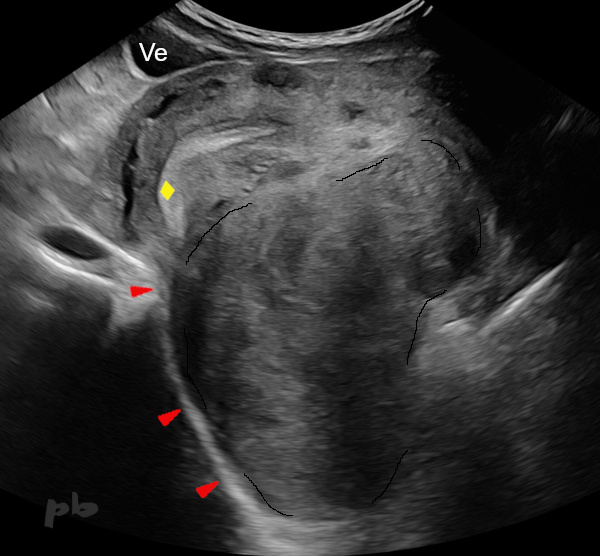

22-Adénomyose externe – Nodule du LUS Droit

Echographie coupe sagittale.

Endométriose profonde sur le torus et le LUS (ligament utéro-sacré droit ►), se prolongeant vers l’avant par une plage hypoéchogène intra utérine et myométriale (★) contenant des spots hyperéchogènes internes : adénomyose externe.

Contour utérin postérieur (►).

Sigmoïde fixé sur le nodule (★).

22-External Adenomyosis – Right USL Nodule

Sagittal ultrasound section.

Deep endometriosis on the torus and the right USL (uterosacral ligament ►), extending forward with a hypoechoic intrauterine and myometrial area (★) containing internal hyperechoic spots : external adenomyosis.

Posterior uterine contour (►).

Sigmoid fixed on the nodule (★)